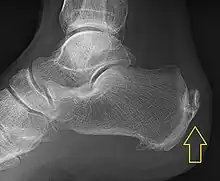

.jpg)

Achilles tendinitis is usually diagnosed from a medical history, and physical examination of the tendon. Projectional radiography shows calcification deposits within the tendon at its calcaneal insertion in approximately 60 percent of cases.[17] Magnetic resonance imaging (MRI) can determine the extent of tendon degeneration, and may show differential diagnoses such as bursitis.[17]

Swelling in a region of micro-damage or partial tear can be detected via usual exam. Increased water content and disorganized collagen matrix in tendon lesions may be detected by magnetic resonance imaging.[18]